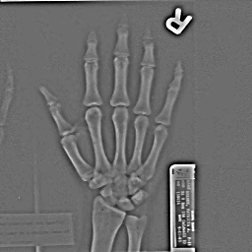

image-369.png image-370.png

Original Hand image Gaussian blur (2.5 pixel radius)

image-371.png image-372.png

Subtracting blur from original Added back to original